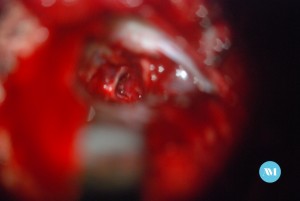

Algunos pacientes pueden requerir cirugía para aliviar la presión sobre el nervio. Las técnicas:

- Cirugía para extirpar un vaso sanguíneo que está ejerciendo presión sobre el nervio trigémino (llamada descompresión microvascular o DMV).